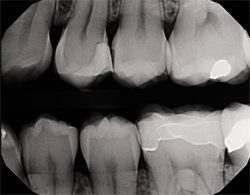

Technology continues to improve the way clinicians diagnose dental conditions and educate patients. The DEXIS™ CariVu™ caries detection device uses near-infrared transillumination technology in a highly visual way. The images produced appear very similar to X-rays except with an added benefit-CariVu does not emit any ionizing radiation. In the resulting images, enamel appears transparent and carious lesions as dark areas. This technology can help identify occlusal, interproximal and recurrent carious lesions and cracks.

The handpiece tip has two soft flanges with NIR lights and a camera for capturing images (Fig. 1). Simply place the tip over the occlusal surface so that the flanges hug the buccal and lingual/palatal aspects of the teeth (Fig. 2) to view live video of teeth (Fig. 3). I can capture an image in one second with a squeeze on the wand. I can also capture short video clips using a “rocking” technique that actually creates a 5-second video of the tooth seen at varying directions instead of just a static image.

Fig. 2 Fig. 3